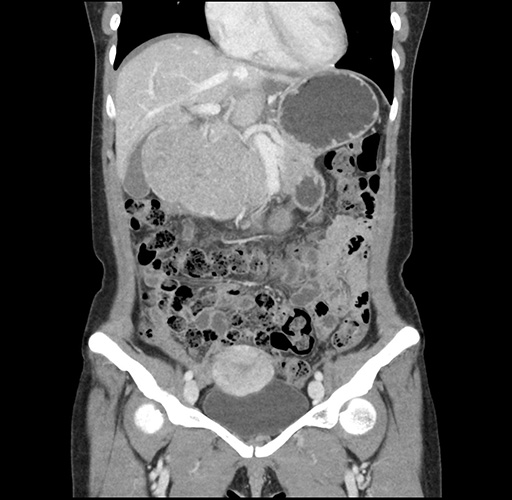

Imaging Analysis

Look through the patient's CT scan to identify any areas of concern for the necessary procedure.

Based on your CT findings, which issue(s) would give reason for "planned slowing down moment(s)" in this case?

Considering a standard left lateral sectionectomy procedure, what step(s) of the operation would you do differently in this case ?